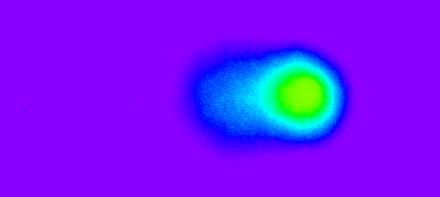

Figure 3.

More DNA damage but the cells are still alive (1 hr of sonication in the presence of encapsulated DOX).